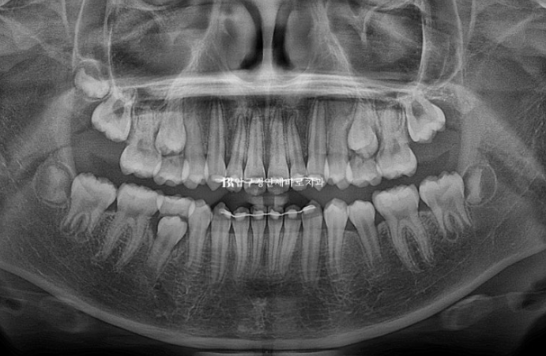

치근평행도도 양호합니다.

1년 2개월간의 변화를 엑스레이로 보면 이러합니다.